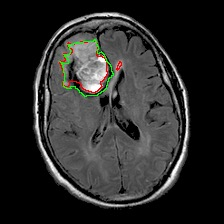

Neural processes have recently emerged as a class of powerful neural latent variable models that combine the strengths of neural networks and stochastic processes. As they can encode contextual data in the network's function space, they offer a new way to model task relatedness in multi-task learning. To study its potential, we develop multi-task neural processes, a new variant of neural processes for multi-task learning. In particular, we propose to explore transferable knowledge from related tasks in the function space to provide inductive bias for improving each individual task. To do so, we derive the function priors in a hierarchical Bayesian inference framework, which enables each task to incorporate the shared knowledge provided by related tasks into its context of the prediction function. Our multi-task neural processes methodologically expand the scope of vanilla neural processes and provide a new way of exploring task relatedness in function spaces for multi-task learning. The proposed multi-task neural processes are capable of learning multiple tasks with limited labeled data and in the presence of domain shift. We perform extensive experimental evaluations on several benchmarks for the multi-task regression and classification tasks. The results demonstrate the effectiveness of multi-task neural processes in transferring useful knowledge among tasks for multi-task learning and superior performance in multi-task classification and brain image segmentation.